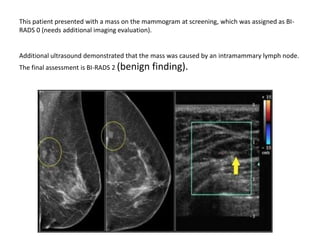

This patient presented with a mass on the mammogram at screening, which was assigned as BI-

RADS 0 (needs additional imaging evaluation).

Additional ultrasound demonstrated that the mass was caused by an intramammary lymph node.

The final assessment is BI-RADS 2 (benign finding).